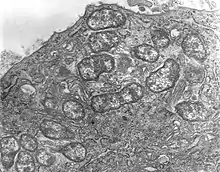

| Orientia tsutsugamushi | |